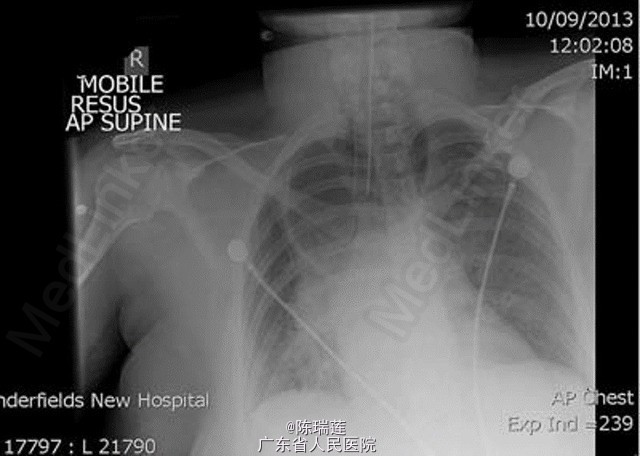

体检发现,患者呼吸急促,但无明显哮鸣音。急救人员初步考虑为哮喘急性加重,给予激素雾化吸入和静脉使用,但症状无好转。 急诊行胸片示右上肺透亮影(图 1)。 行肺部 CT 示食管内有大量食物,呈显著扩张状态;严重压迫气管及气管内插管(图 2)。拔管后行胃十二指肠镜检查,未发现存在梗阻。